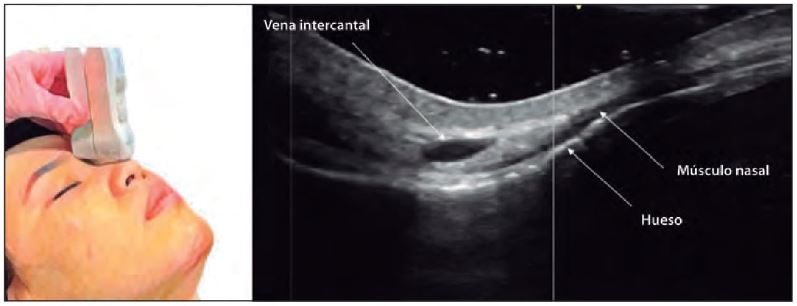

Un conocimiento profundo de la anatomía nasal es indispensable para realizar procedimientos seguros. La ecografía permite visualizar:

- Capas de tejido: Epidermis, dermis, hipodermis, SMAS, huesos y cartílagos.

Para obtener imágenes detalladas, se recomienda:

- Transductores lineales de alta frecuencia (12-24 MHz).

- Evitar presión excesiva sobre la sonda para no comprimir vasos.